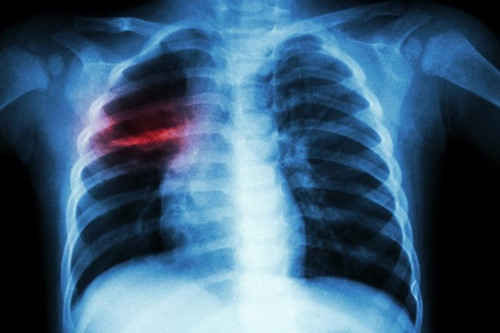

Một ca viêm phổi nặng do biến chứng của thủy đậu.

Viêm phổi là một trong những biến chứng nguy hiểm nhất của thủy đậu với biểu hiện là ho ra máu, khó thở, thở nhanh, sốt cao. Nếu không chữa trị kịp thời, biến chứng thủy đậu có thể gây tử vong..

Thực tế đã từng có trường hợp bác sĩ tại Đồng Tháp tử vong vì thủy đậu. Theo các bác sĩ Bệnh viện Bệnh nhiệt đới TPHCM, bệnh nhân được chuyến đến bệnh viện trong tình trạng viêm phổi quá nặng, suy hô hấp và không qua khỏi.